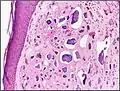

| Micrograph of calcinosis cutis. The calcification is purple (bottom of image). H&E stain. | |

Calcinosis cutis is a type of calcinosis wherein calcium deposits form in the skin. A variety of factors can result in this condition. The most common source is dystrophic calcification, which occurs in soft tissue as a response to injury. In addition, calcinosis is seen in Limited Cutaneous Systemic Sclerosis, also known as CREST syndrome (the "C" in CREST).[1] In dogs, calcinosis cutis is found in young, large breed dogs and is thought to occur after a traumatic injury.